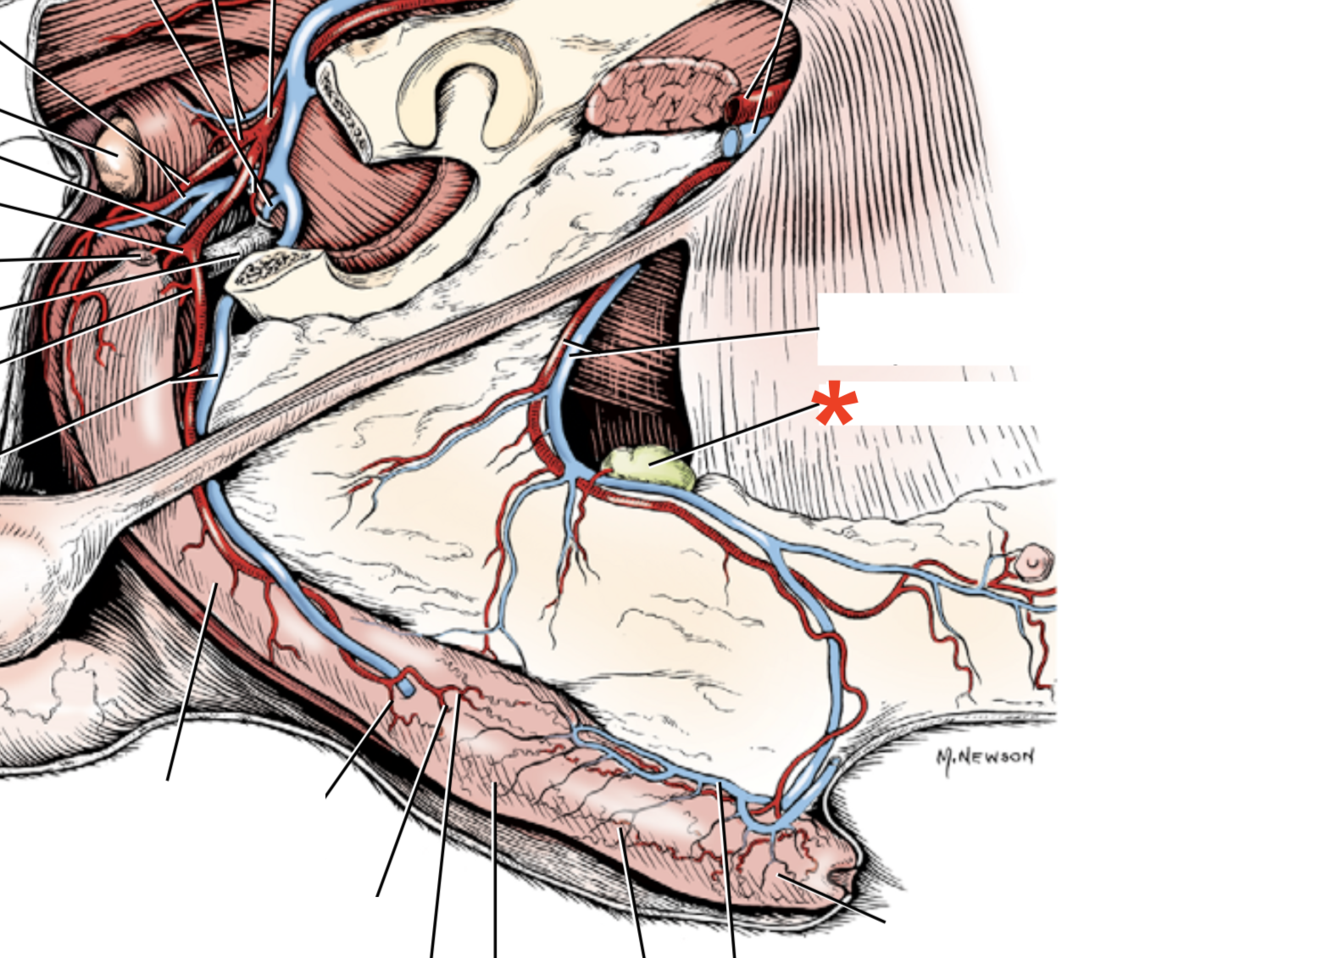

1

A

Crus mediale

Processus vaginalis

A./v. pudenda externa

Processus vaginalis

Tr. pudendoepigastrica

- A. pudenda externa

- A. epigastrica caudalis

A./v. pudenda externa

- Through canalis inguinalis

- Branches: a. epigastrica caudalis superficialis

A. epigastrica caudalis

- Supplies m. rectus abdominis

- Through canalis inguinalis

- Branches:

- **A. labialis/scrotalis ventralis

Ln. inguinalis superficialis

- Males: Embedded in fat between abdominal wall and thigh

- Females: Cranial to proc. vaginalis, under gl. mammaria

**Tunica vaginalis**

29

**Proc. vaginalis**

30

**Lig. teres uteri**